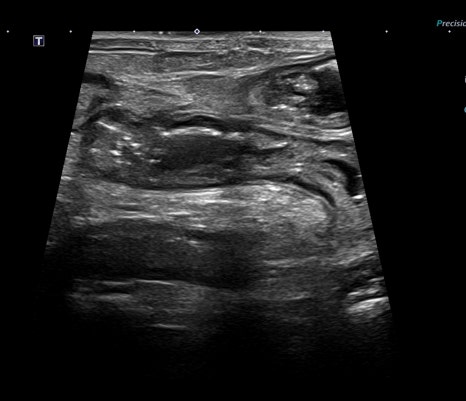

복부 초음파: 위장염, 미란 소견

- 복부 초음파: 위장염, 미란 소견